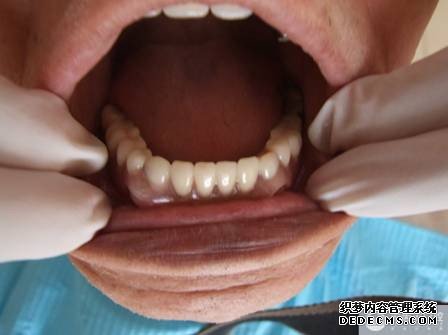

医生诊断:经过3D数字化全景机的详细检查,了解到黄婆婆的牙槽嵴条件较好,加之要保留基牙,经过商量决定,选定球帽式精密附着体修复,黄婆婆及家人也同意了该修复方案。 初诊片

取牙颌模型    义齿加工成型 义齿加工成型    戴入口内 戴入口内    修复完成 修复完成

案例回访:经过活动修复,黄婆婆不仅恢复了部分咀嚼功能,同时还恢复了发音功能。患者非常满意,前不久还派她儿子到我院表示感谢,到目前已修复了2年多,使用情况依然良好。